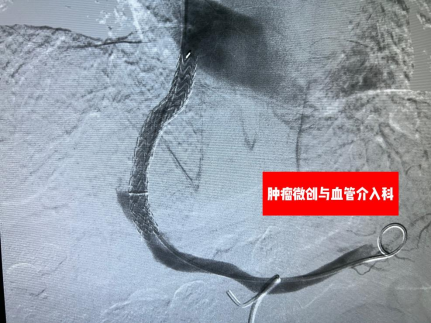

据徐兴鲁主任介绍,TIPS手术最大的优势在于微创,通常经颈静脉途径穿刺,通过在肝静脉与门静脉之间的肝实质内建立分流道,以微创的方式从结构上显著降低门静脉阻力。该手术广泛应用于肝硬化门静脉高压所致的食管胃静脉曲张破裂出血、顽固性胸腹水、肝窦阻塞综合征、门静脉血栓等疾病治疗,对部分急危患者能起到立竿见影的效果。科室曾采用该技术救治过一名49岁男性消化道大出血病人,术前患者门静脉高压并发食管胃底静脉曲张,到达医院急诊科时已经休克,生命垂危,急需采取经颈静脉门腔分流术(TIPS)救治。在征得患者家属同意后,徐兴鲁团队在急诊科、麻醉科、手术室医护人员的配合下,连夜在最短的时间内成功为病人“搭桥”,在门静脉与肝静脉之间植入一枚8í80mm的覆膜支架,门静脉血流引流回到下腔静脉,压力下降,出血停止,患者生命得以挽救。看着醒来的患者,病人家属激动的无以言表。